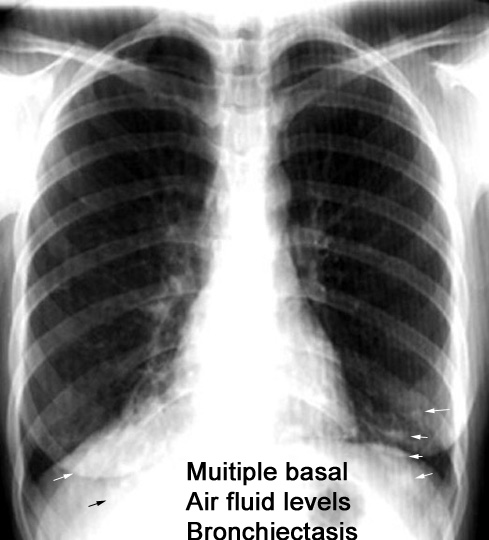

Case 10 Labeled Image What is the differential for multiple cavities?